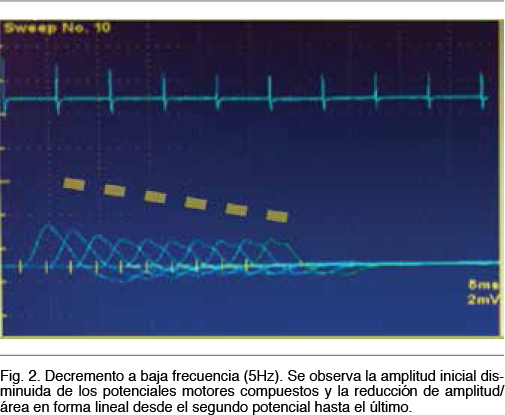

Se observa una neuroconducción sensitiva con latencias distales, amplitudes y velocidades de conducción normales. El electromiograma fue normal. Del estudio de neuroconducción motora destacamos la presencia de potenciales motores bien configurados, de latencias normales, con velocidades de conducción motora normales y sin bloqueos de la conducción, pero con amplitudes reducidas en 4 miembros. Se realiza una breve contracción isométrica de 15 segundos y se procede a la estimulación motora nuevamente, observandose un incremento de la amplitud a rangos normales. El incremento de amplitud obtenido fue > 100% para nervio motor Mediano (Figura 1). En el estudio de transmisión neuromuscular repetitiva realizado en el nervio motor Cubital se observa un decremento en el tren de potenciales obtenidos a baja frecuencia (5Hz) en un 33% entre el primer potencial y el cuarto potencial y con una morfología del tren en descenso lineal (Figura 2). El cociente de decremento tardío / decremento temprano fue de 102%. A alta frecuencia (30Hz) se observo un incremento de la amplitud de un 635% entre el primer potencial y el potencial número 100 (Figura 3).